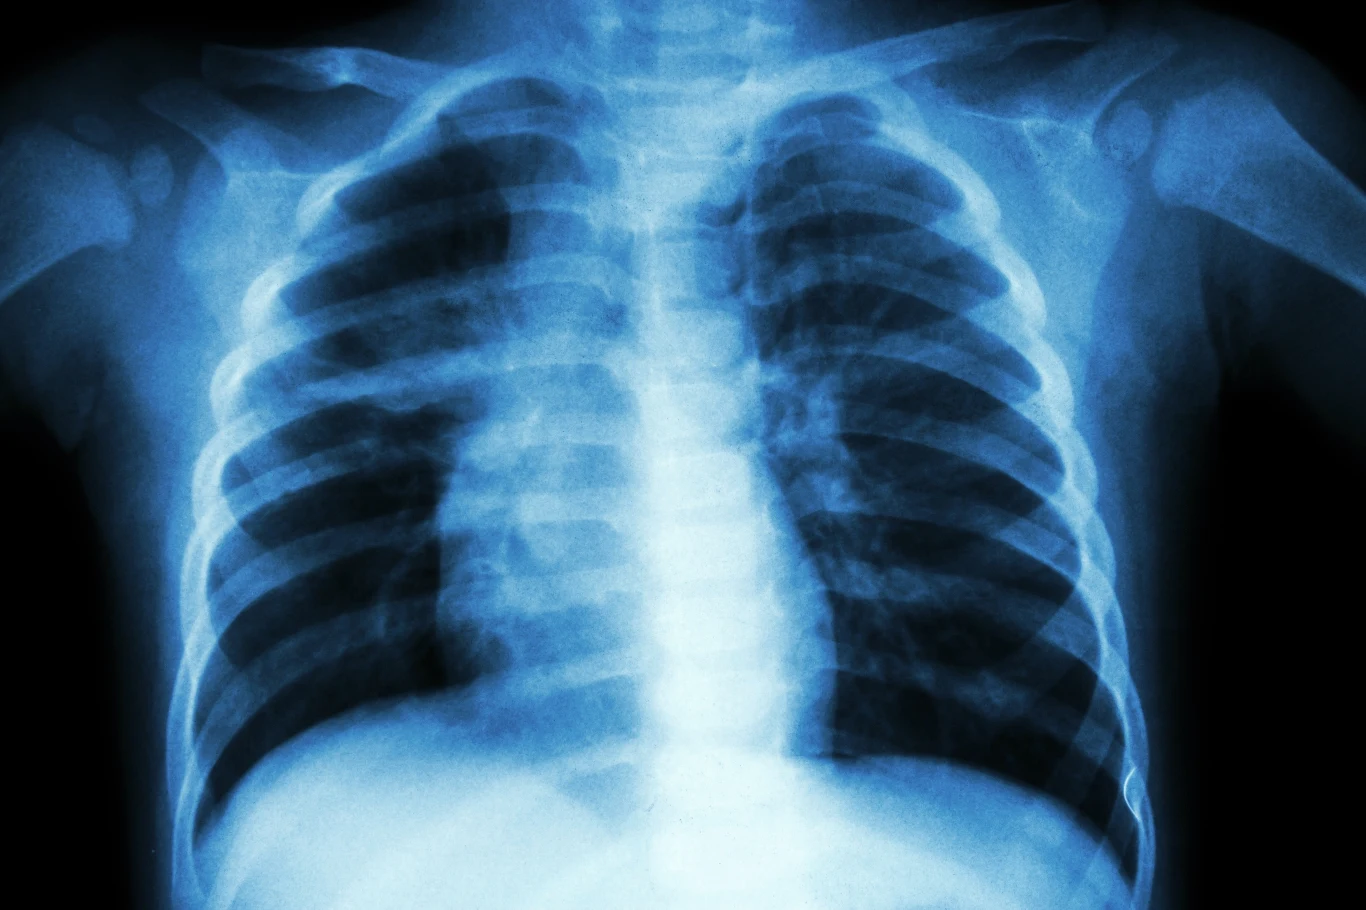

Tłuszcz zapycha drogi oddechowe

Jeżeli przesadzisz z kaloriami i zrezygnujesz z ćwiczeń, tkanka tłuszczowa odłoży się nie tylko na brzuchu. Okazuje się, że drogi oddechowe, łącznie z płucami, również mogą zapchać się komórkami tłuszczowymi.

Naukowcy z Uniwersytetu Australii Zachodniej w Perth po raz pierwszy znaleźli dowody na to, że tłuszcz może gromadzić się w płucach osób cierpiących na nadwagę i otyłość. Osoby z nadwagą częściej cierpią na świszczący oddech i mają problemy z oddychaniem, jednak sądzono, że wynikało to z nadmiaru tłuszczu wywierającego nacisk na klatkę piersiową. Okazuje się jednak, że w ich ciałach może występować inny mechanizm. To z kolei rzuca nowe światło na domniemane powiązania astmy z otyłością.Naukowcy przeprowadzili badanie płuc 52 zmarłych osób. Przyczyną zgonu 16 z nich była astma. 21 osób miało astmę, ale zgon nastąpił z innego powodu, a 15 nigdy nie doświadczyło żadnych objawów astmy. Naukowcy zbadali próbki pod mikroskopem i ocenili ilościowo poziom tkanki tłuszczowej obecnej w ścianach dróg oddechowych płuc. Następnie porównali to ze wskaźnikiem masy ciała (BMI) każdej z osób.Odkryto bezpośrednią korelację między BMI a poziomem tłuszczu w płucach. Im większa była nadwaga, tym więcej komórek tłuszczowych można było znaleźć w ścianach dróg oddechowych. Odkryto także, że wzrost tłuszczu zmienia normalną strukturę dróg oddechowych i prowadzi do stanów zapalnych w płucach, co prowadzi do poważnych problemów zdrowotnych.

- Odkryliśmy, że nadmiar tłuszczu gromadzi się w ścianach dróg oddechowych, gdzie zwiększa stan zapalny. Może to powodować pogrubienie dróg oddechowych, co ogranicza przepływ powietrza do i z płuc, a to przynajmniej częściowo wyjaśnia wzrost objawów astmy - powiedział prof. Peter Noble, jeden z autorów badań.Nie zostało jeszcze udowodnione, że astmę można leczyć poprzez utratę masy ciała. Konieczne jest przeprowadzenie dodatkowych badań.